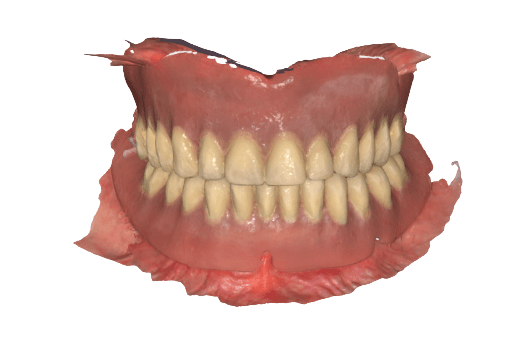

3.4 Adaptation of the wax-up by the dental lab and receiving STLs for in-house production

While the patient is in the dental chair, the dental lab adjusts the wax-up considering the intraoral data with the final implant positions in exocad. The temporary full-arch implant-supported prosthesis are then exported as STL files and sent via email to the clinic for in-house manufacturing.

Temporary full-arch implant-supported appliances for the upper and lower arch designed in exocad upon the digital patient.

3.5 In-House 3D Printing of Dental Prosthesis

Once the files are received in the dental clinic, they are prepared to print using PreForm Dental and then sent to the Form 4B 3D printer for printing. For the appliances, Premium Teeth Resin was used to print both upper and lower temporary full-arch implant-supported appliances at 100 microns layer height setting — this  took 29 minutes total.

Premium Teeth Resin was chosen as it is a ceramic-filled, Class IIa material with optimized esthetics, and mechanical resistance. The total print time is very convenient for manufacturing  same-day full-arch rehabilitations.